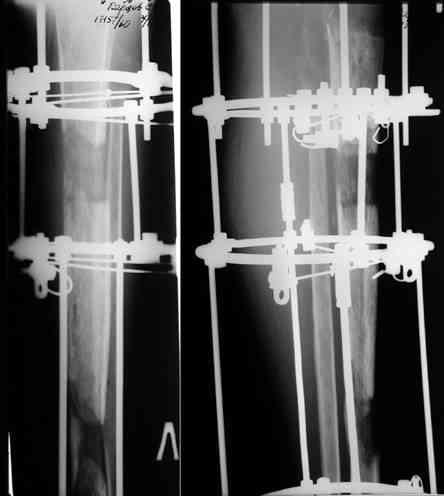

Этот стиль мне полностью приемлем и понятен. Наверно я бы поступил также. Но статистика упрямая вещь. Сколько у тебя или у другого врача опыта по замещению дефектов бедра? У меня за 25 лет работы 3, и еще около 15 случаев удлинения бедра. Случай у тебя очень сложный. Если Вы выбираете Илизаровскую методику то надо на в/з хорошую дугу, не менее 4-5 спиц с напайками.Стержни хороши когда кость не измучена и на 2-4 месяца. Здесь аппарат на 6-8 месяцев. Если есть желание я только за, и

Прикрепляю пример замещения дефекта бедра 20 см, после резекции по поводу опухоли, эндопротеза Сиваша, вялотекущего остеомиелита со свищами в течении 3 лет. Получилось хорошо и всего за 6 месяцев в аппарате. Колена не было. У Вас случай сложнее. Это было в 1998г. Я работал в ЦИТО и у меня было 4 больных, я занимался им с утра до ночи. Сейчас 60 больных и операций в нашем отделении 25-30 в неделю.Если могу чем помочь - нет проблем.